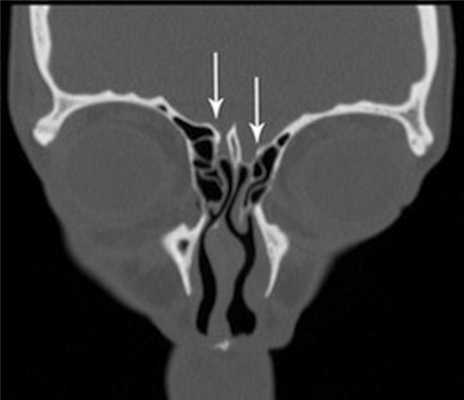

(Слева) На аксиальной КЛКТ справа и слева визуализируются добавочные устья ниже уровня соответствующих крючковидных отростков. Основные устья находятся на другом уровне и не видны на этом срезе.

(Справа) На корональной КЛКТ у этого же пациента визуализируются дополнительные устья справа и слева. Основные устья на этом срезе не видны. Обратите внимание на субтотальное снижение пневматизаци левой верхнечелюстной пазухи.